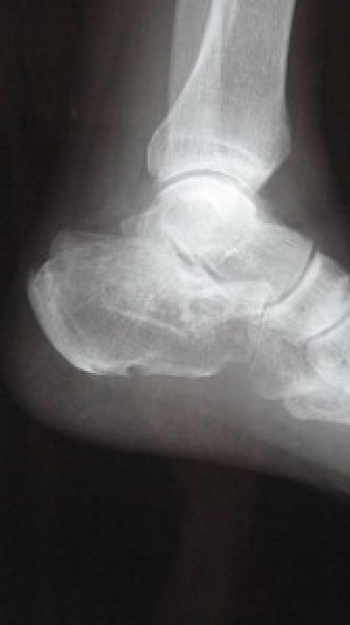

踵骨骨折

踵骨は足根骨の中で最大の骨で、歩行時に最初に接地する部位に位置し、足根骨骨折中もっとも頻度が高い。

距骨などと複雑な形態の関節面を有するため、骨折が生じると関節内骨折を起こしやすい。

また、周囲を腱・神経も多数経過しており、そのため後遺症も起こしやすい。

発生機序により脊椎椎体圧迫骨折も合併することがある

分類は、関節外骨折、関節内骨折がある。